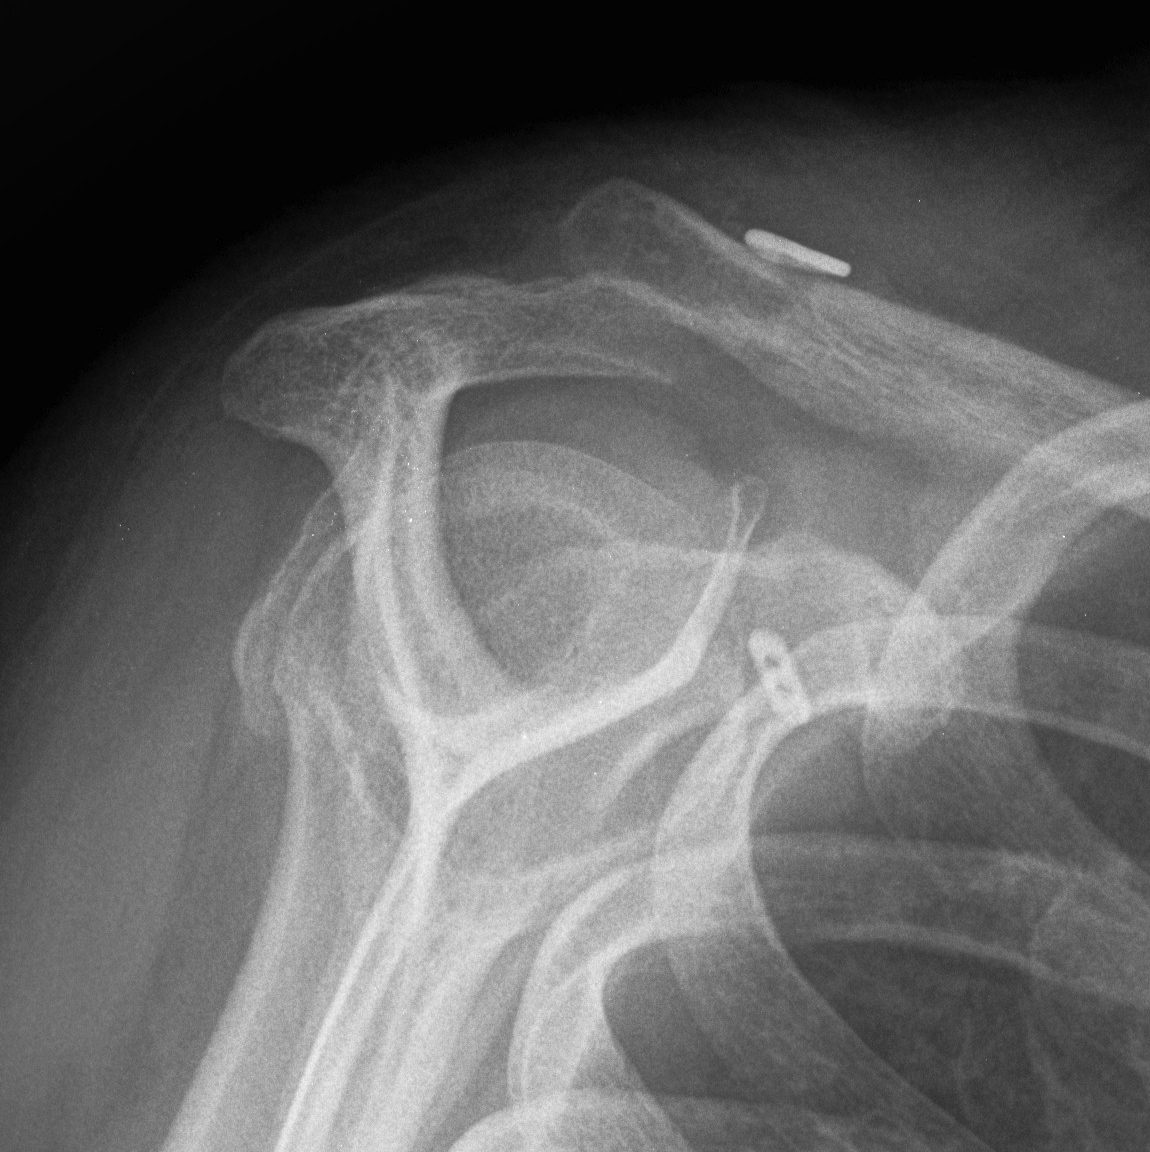

V High dislocation (100 - 300% CC distance) - disrupted trapezius & deltoid and end of clavicle subcutaneous